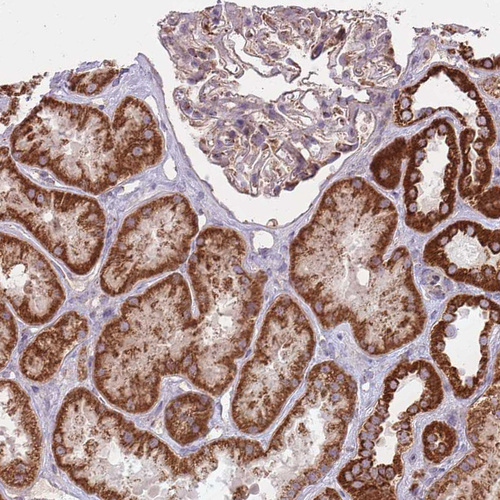

Immunohistochemical staining of human thyroid gland shows strong granular cytoplasmic positivity in glandular cells.